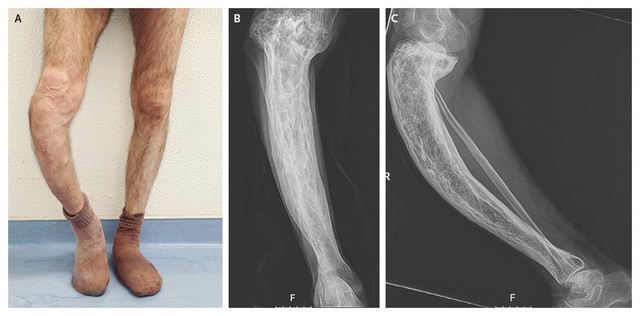

Viêm xương là tình trạng viêm và phá hủy xương do vi khuẩn (nguyên nhân chủ yếu), virus hoặc vi nấm gây ra. Các triệu chứng phổ biến bao gồm đau và yếu cục bộ với các triệu chứng cơ năng thể trạng (trong viêm tủy xương cấp tính) hoặc không có các triệu chứng cơ năng (trong viêm tủy xương mãn tính). Chẩn đoán thông qua hình ảnh học và nuôi cấy vi khuẩn. Điều trị bằng thuốc kháng sinh và đôi khi cũng cần phẫu thuật.